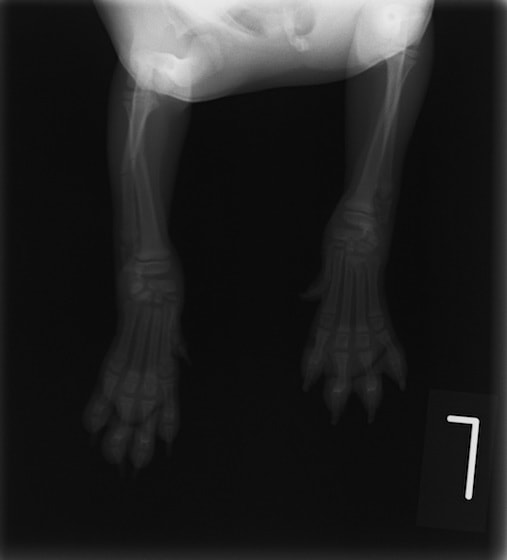

ペルシャ猫 11ヶ月齢 雄

他院にて左大腿骨遠位の成長板骨折(salter-harrisⅠ型)が認められており、治療相談を目的として来院。当院にて、キルシュナーワイヤーを用いたピンニングにより骨折部位の整復を行いました。術後の経過は良好で、現在も経過観察中です。

術前レントゲン

術後レントゲン